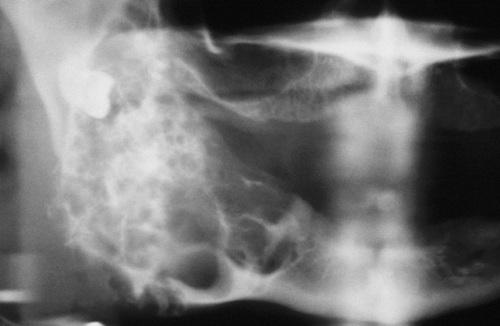

This large, multilocular cyst involves most of the ascending ramus and is growing in an anteroposterior direction.

odontogenic keratocyst (OKC)